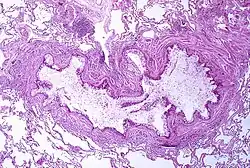

Obstrução do lúmen de um bronquíolo com exsudato, metaplasia da célula caliciforme e espessamento da membrana basal numa pessoa com asma.

A asma é o resultado da inflamação crónica das vias respiratórias, a qual provoca uma contração crescente dos músculos lisos envolventes. Isto provoca o estreitamento das vias e os sintomas clássicos do som sibilante ao respirar. Este estreitamento é geralmente reversível, com ou sem tratamento. Ocasionalmente, verificam-se alterações nas próprias vias respiratórias.[31] As alterações mais vulgares são o aumento de eosinófilos e o espessamento do tecido linfoide. Em casos crónicos, o músculo liso das vias respiratórias pode aumentar de tamanho, a par de um aumento do número de mucosas. No processo estão também envolvidos outros tipos de células, como os linfócitos T, macrófagos e neutrófilos, e outros componentes do sistema imunitário, como citocinas, quimiocinas, histamina e leucotrienos.[17]